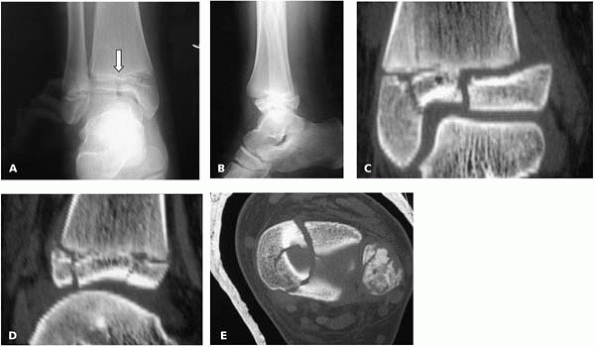

triplane fracture with any displacement seen on plain films (Fig. 9-19).

![]() |

▪ FIGURE 9-19 A: AP view of a triplane fracture. Note that on the plain radiographs the intraarticular component of the fracture (arrow) does not appear to be very displaced or have a stepoff. B: Lateral view of fracture. C, D, E: CT further reveals extent of intraarticular stepoff and comminution.

|